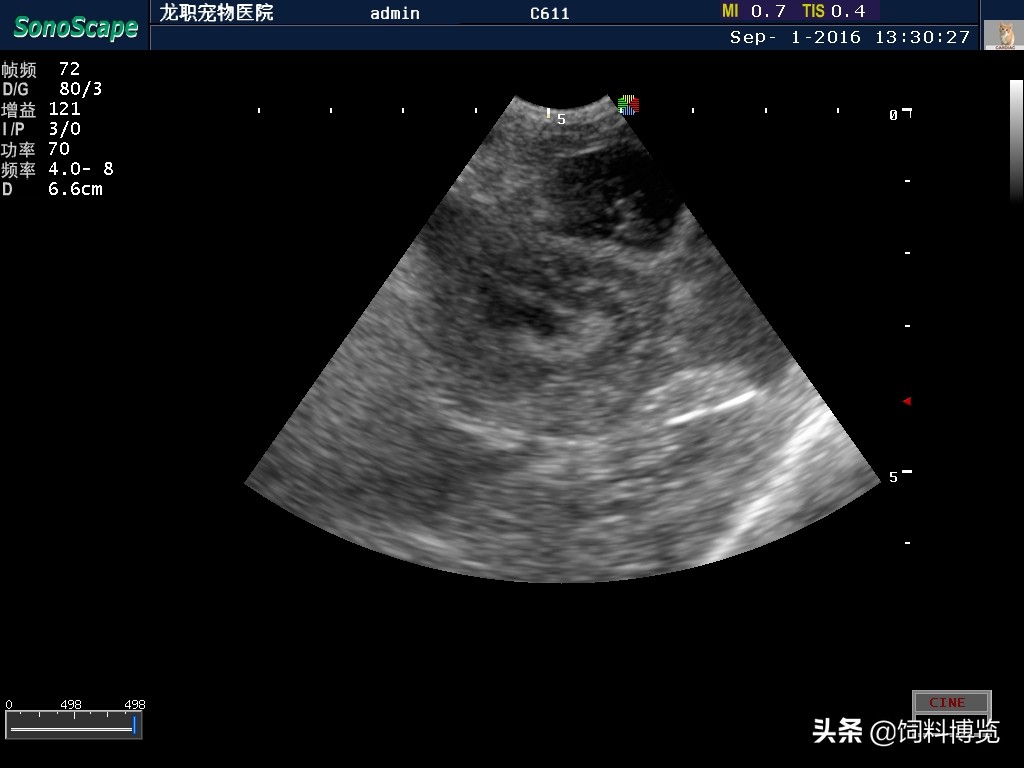

2.3超声检查 腹腔内见大量液性暗区,子宫壁增厚,子宫腔内有液性暗区,其他未见异常。

一般临床上认知的子宫蓄脓为孕酮所引发,而孕酮对于子宫的作用包括有抑制子宫内白细胞的反应,降低子宫肌层的收缩,刺激子宫内膜腺腺体的发育,这些都是为了怀孕而准备的作用,但如果怀孕没有成立,或根本没有配种是,这些作用就可能变成有危害,使得细菌逆行性感染容易发生子宫蓄脓。子宫蓄脓在影像学的诊断上还是以腹腔超生波扫描为主。本病例中,腹腔超生波扫描可见到膨大的官腔样影像,官腔增厚,不规则,内有低回声性的液性暗区,并有腹腔积液表现,白细胞数及中性粒细胞数目显著升高,确诊子宫蓄脓。诊断结果提示需要尽早手术并进行对症及支持疗法,建立输液管道来补充脱水及纠正离子平衡。经手术打开腹腔,发现子宫与周围脏器发生多处黏连,确诊为子宫残端蓄脓并发腹膜炎。手术切除卵巢和残存的子宫,并进行腹腔冲洗,术后恢复较好。